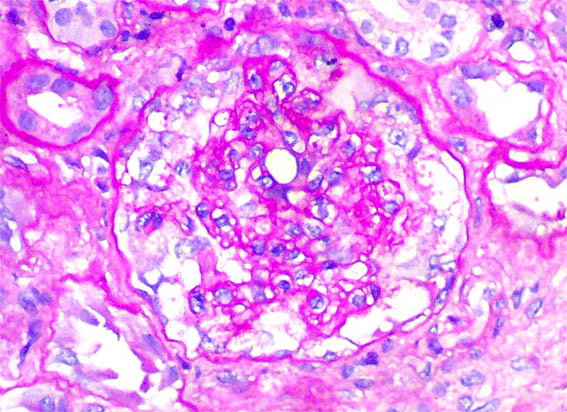

Figure 6.

PAS,

X400.